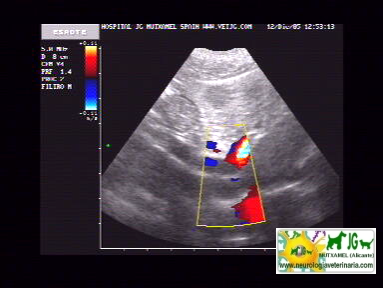

intentamos buscar el shunt portosistémico, pero no es visible ni con el doppler |

Se aprecia la vena porta muy aumentada de tamaño y sinuosa, por lo que es previsible que haya shunts, aunque no los distingamos |

video de ecografía con doppler: |